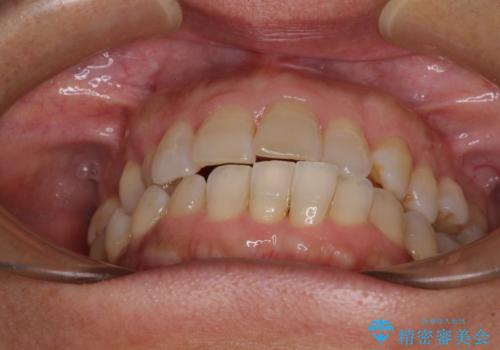

骨格のずれをカムフラージュ クロスバイトのワイヤー矯正

- 骨格的な咬み合わせのズレ、前歯のデコボコとクロスバイトを気にして来院された患者様です。

奥歯の噛みにくさが顕著なためマウスピースではなく、ワイヤー装置による矯正治療を行うこととしました。

下顎の正中を歯1本分ずらした位置とすることで、外見上の骨格的なずれをカバーするように計画しました。

クロスバイトを改善したことで、前歯の負担が軽減し、安定して噛めるようになりました。